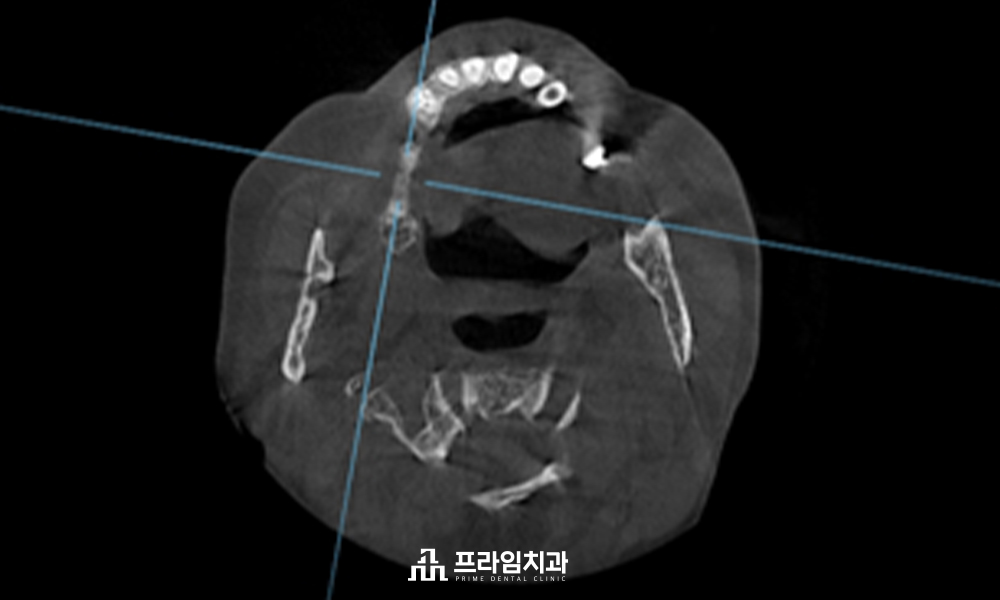

저희 치과에서는 임플란트

식립 전 3D CT와 구강 스캐너를

활용하여 육안으로 판단하기

힘든 구강 해부학적 구조물과

혈관 및 신경의 위치까지 면밀히

파악하여 1:1 맞춤 치료 계획을

수립하고 있습니다.